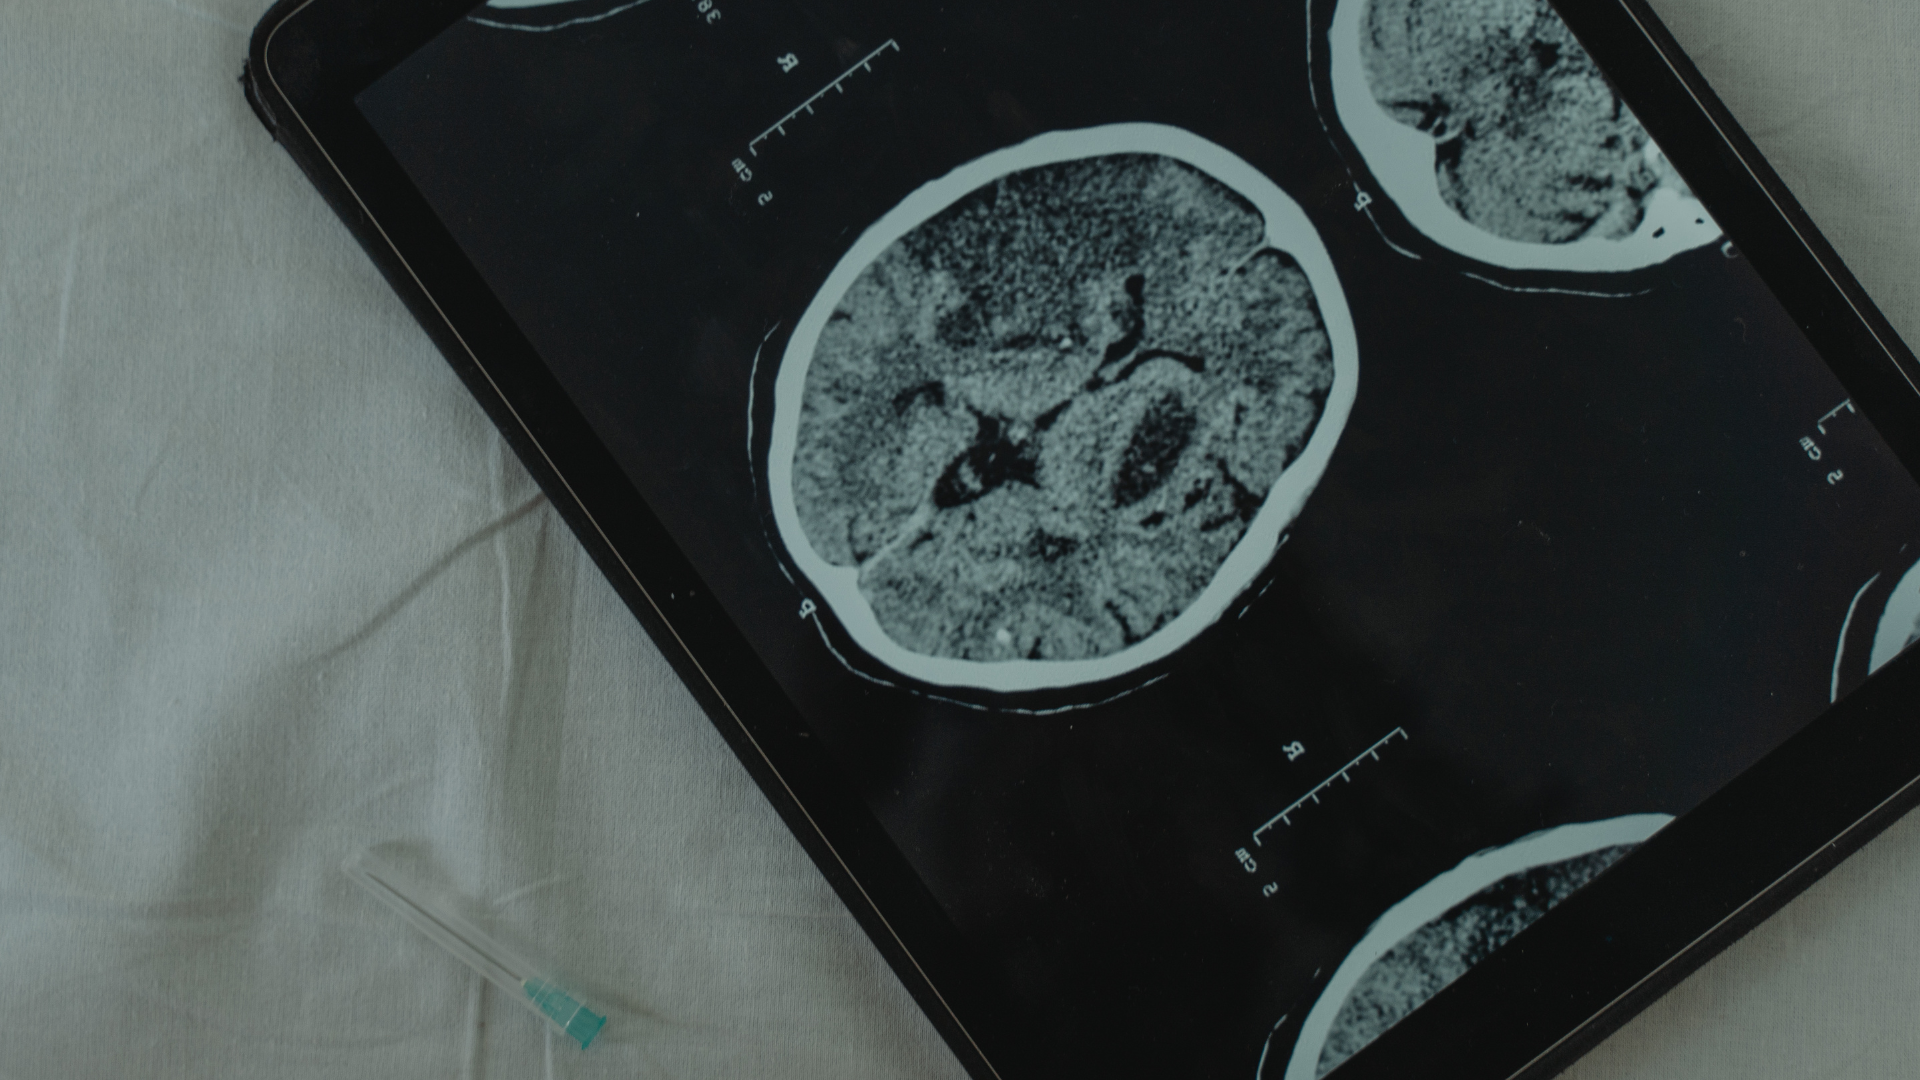

Kanserde Tanı ve Tedavi

Kanser tedavisi ve tanısı birçok uzmanlık dallarının iş birliğini gerektirmektedir. Cerrahi ve radyoterapi lokal tedavi yöntemleri olup, onların arkasından kemoterapi ve immünoterapi gibi sistemik tedaviler uygulanmaktadır.